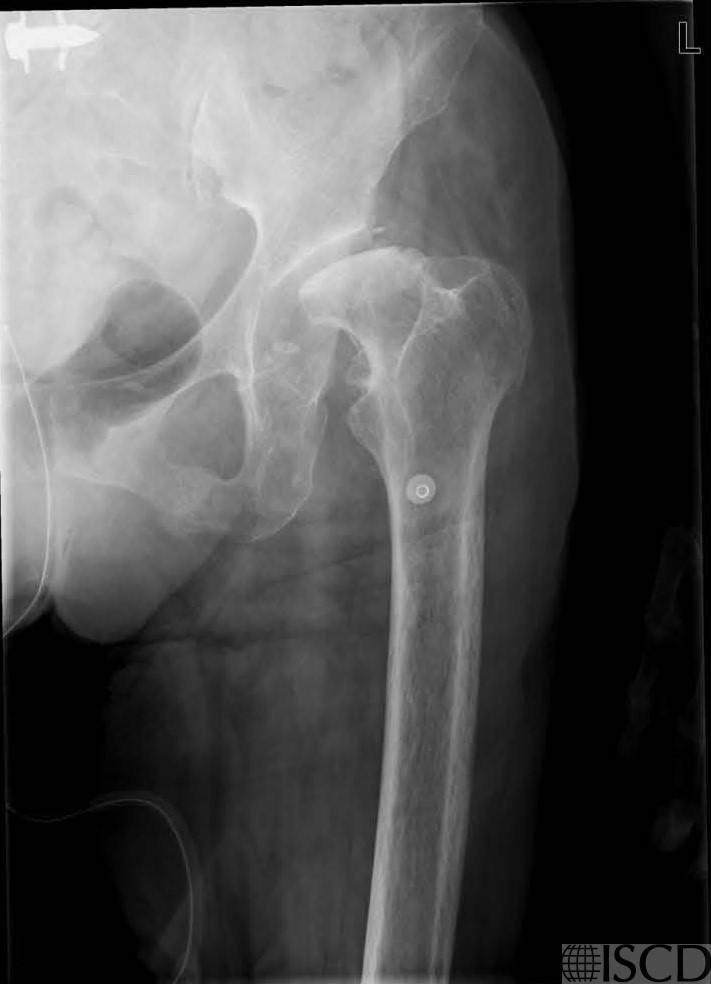

This is the accompanying hip radiograph showing avascular necrosis of the left femoral head.

These images show a baseline DXA and a follow-up DXA 8 years later in a patient who had intervening thyroid storm and was placed on chronic steroids for rheumatoid arthritis. The follow-up image shows avascular necrosis with collapse and remodeling. There is a significant decrease in bone mineral density in the 8 years after starting steroids and thyroid storm. It was not possible to rotate the hip internally to the same extent as on the baseline scan because of the change in hip anatomy.